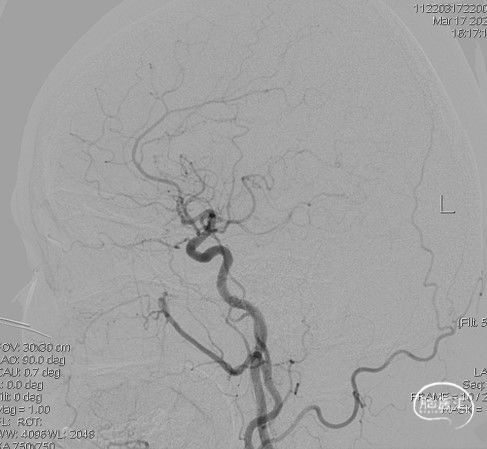

造影:右侧颈内动脉末段变细,右侧大脑中动脉M1段分叉前重度狭窄,豆纹动脉增多,右侧大脑前动脉向大脑中动脉分布区代偿供血:

右侧颈内动脉正位:

右侧颈内动脉侧位:

三维重建显示右侧大脑中动脉分叉前部重度狭窄,狭窄段直径0.4mm,狭窄程度约84%:

左侧颈内动脉末段、大脑前动脉A1段、大脑中动脉M1段变细:

左侧颈内动脉正位:

左侧颈内动脉侧位:

总结:在降压药降压的“加强试验”条件下,发现右侧为主的双侧三分叉部位狭窄,右侧大脑半球血流动力学相关腔梗。